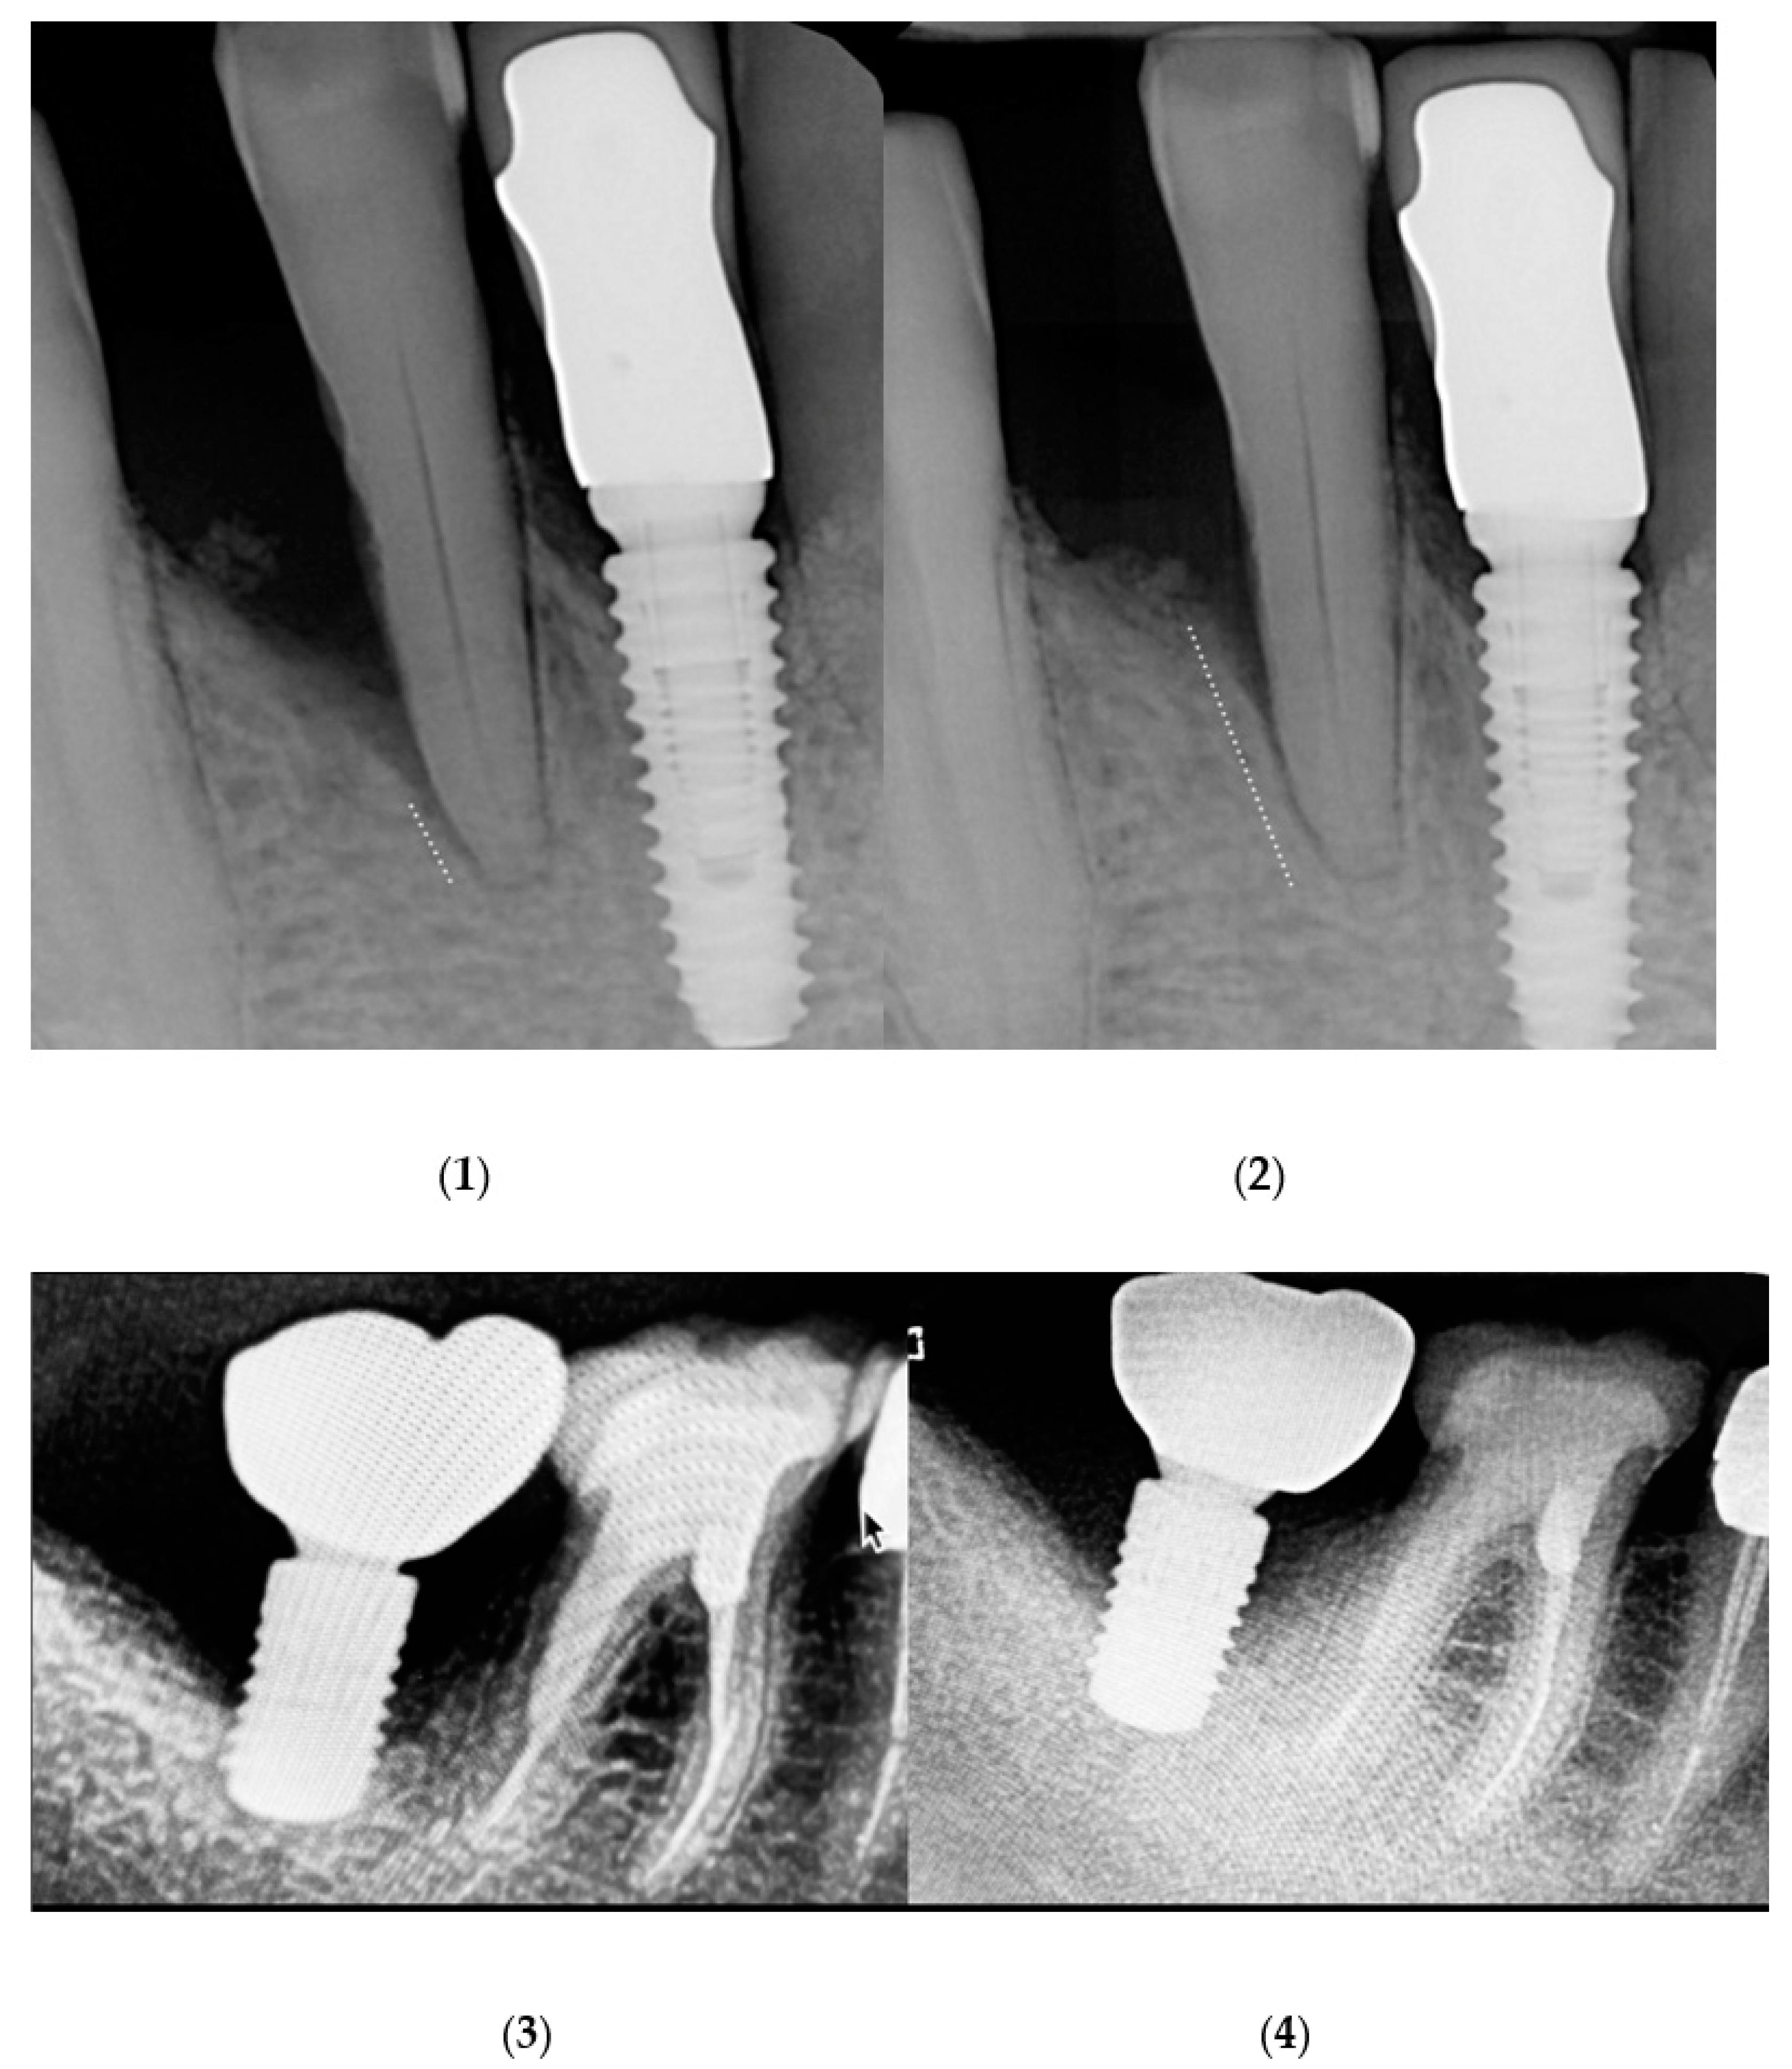

2.2. Results on Peri-Implant Sites

3.2. PDT in Peri-Implantitis